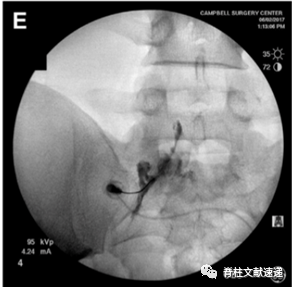

骶1神经根通过腰5/骶1椎间孔阻滞时会可能同时阻滞腰5神经根,不能精确鉴别,故阻滞骶1神经根可通过骶1孔来实现。具体操作如下。

2.1.  俯卧位,常规消毒,定位,正位时调整C臂机,与L5/S1椎间隙平行,黑圈所示为骶1孔,后孔易与较大的前孔混淆(上图A)

2.2.  先将穿刺针扎中骶1孔远端的骶骨(上图B),再逐渐滑行调整至骶孔(上图C)。

2.3.  侧位透视,针尖不应该位于骶管腹侧,理想的位置是紧贴S1椎弓根尾下缘,位于椎板下约5mm(上图D)。

2.4.  穿刺位置良好后,抽吸测试,若无血液和脑脊液,可行造影剂观察(上图E、),再行局麻药物注入。